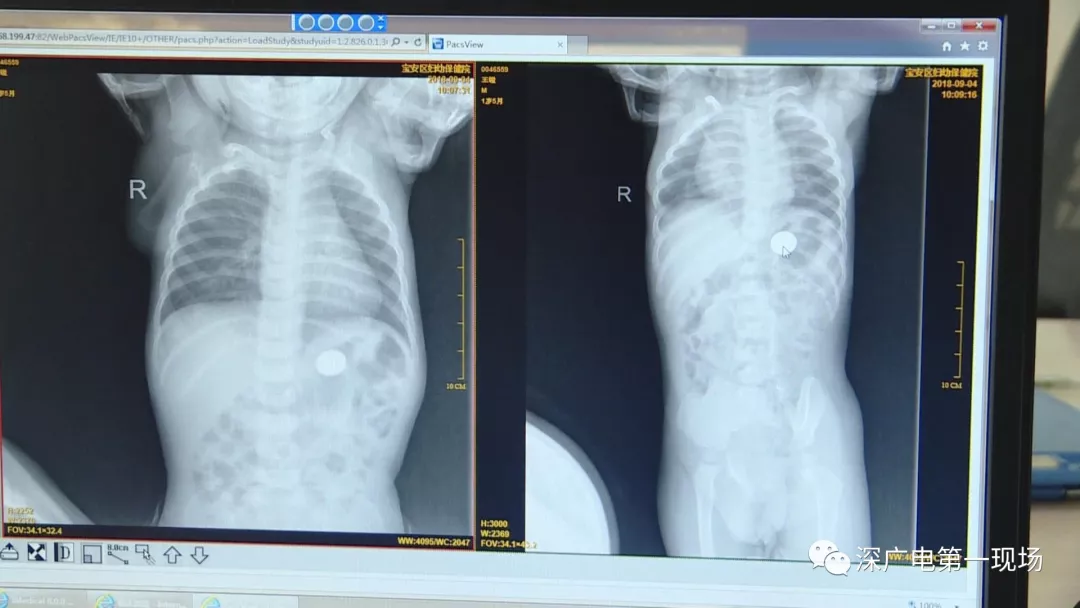

孩子的胸片中有了意外發(fā)現(xiàn)

9月4號,一名1歲零5個(gè)月的男嬰因在家中摔傷,被父母送到了寶安區(qū)婦幼保健院,醫(yī)生診斷為左側(cè)尺橈骨骨折。在進(jìn)行全麻手術(shù)之前,院方例行對嬰兒進(jìn)行了周身檢查。手術(shù)前,兒外科醫(yī)生趙冠聰在查看患者的胸片時(shí),發(fā)現(xiàn)這名嬰兒的胃部有一枚硬幣大小的暗影。

胃部取出一角硬幣

已吞咽半月之久

經(jīng)過兩個(gè)小時(shí)的時(shí)間,兒科醫(yī)生郭景濤為患兒取出了藏在胃底的一角錢硬幣。目前,患兒已經(jīng)痊愈出院。